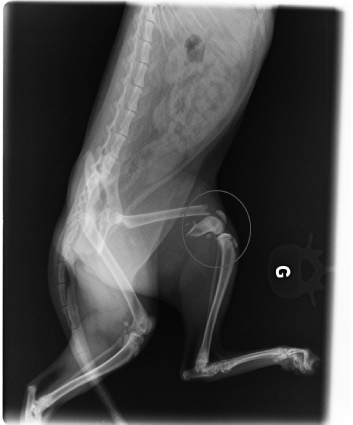

ZOE

Zoé née en 2016 a été percutée par une voiture. Le fémur a été pulvérisé. La pose de 3 broches a permis de réparer sa patte.Après un séjour en cage de convalescence pour éviter les sauts,  Zoé peut de nouveau marcher sans souffrir. Cette petite chatonne a été d’un courage et d’une patience exemplaires.

Zoé est très affectueuse, intelligente et enjouée.